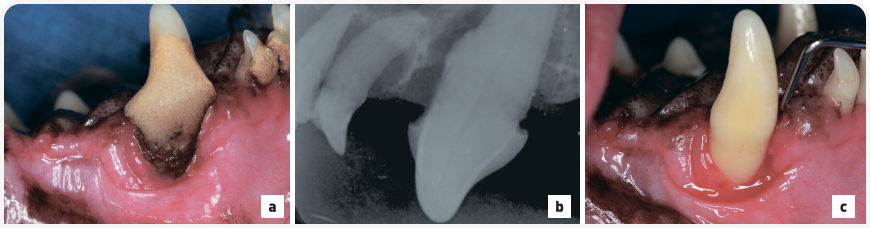

Рисунок 5. (a) Метис мальтийской болонки под общей анестезией в дорсальном лежачем положении; на левом клыке верхней челюсти присутствуют крупные отложения зубного камня, сопровождающиеся рецессией десны. (b) Внутриротовая рентгенография зубов (левая латеральная проекция клыков, техника деления угла пополам) показала 80%-ную вертикальную потерю кости левого клыка верхней челюсти, указывающую на ороназальный свищ. Рентгенограмма также показала практически полную потерю прикрепления второго левого резца верхней челюсти с легкой дилацерацией корня и 80%-ную горизонтальную потерю кости третьего левого резца верхней челюсти, характеризующегося микродентизмом. Первый и второй левые премоляры верхней челюсти отсутствуют. Наблюдаются большие отложения зубного камня на коронке левого клыка верхней челюсти, у которого отмечается аномально прямое строение корня. (c) Левый клык верхней челюсти после удаления зубного камня; пародонтальный зонд вводится передненёбно и демонстрирует глубину свыше 12 мм, что указывает на ороназальный свищ.

Собаки мелких пород, особенно таксы или карликовые пудели, предрасположены к развитию ороназальных свищей в области клыков верхней челюсти, хотя свищи могут образовываться в области любого зуба и у собак любых пород. Ветеринарный врач должен предположить наличие ороназального свища, если владелец описывает такие симптомы, как чихание, особенно во время питья или еды, и слизистые, водянистые или сукровичные выделения из носа. Пластика ороназального свища чаще всего проходит неудачно из-за того, что хирургический лоскут слишком маленький и/или наблюдается натяжение швов. Более того, врач должен аккуратно удалить эпителизированный край дефекта, чтобы обеспечить заживление свежих раневых краев ткани.